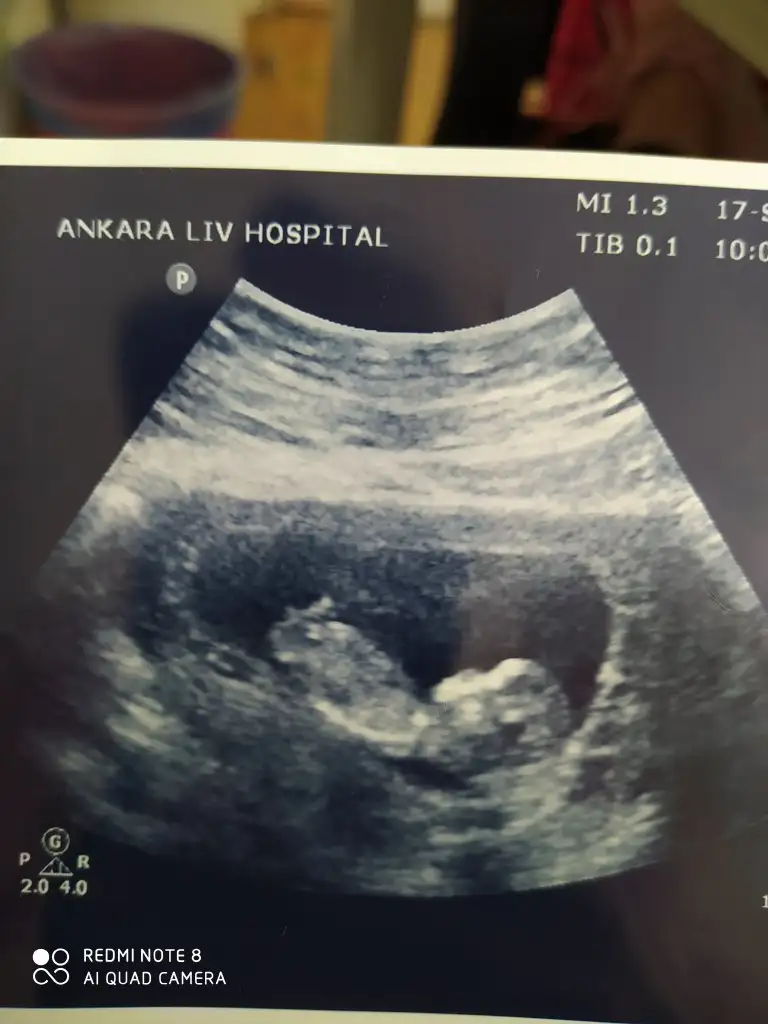

Sağlıkla gelsin cnmBugün doktor kesin kız dediIkra meyra oylamıştım zaten seni yine de söyliyim dedim çok foto attım sana hatta bak bu da son bugünki

Canım bugün geldi bu ultrason doktor ölçüm de yaptı. 27 cm dedim nub açısı. O yüzden net kız da diyemem erkek de dedi. Senin yorumun nedir?Nubu çok karışık net varsa paylasin

Evet nubu karşıya bakıyor canım erkek gibi %60 ihtimal olabilirCanım bugün geldi bu ultrason doktor ölçüm de yaptı. 27 cm dedim nub açısı. O yüzden net kız da diyemem erkek de dedi. Senin yorumun nedir?

Sağolasın kuzumEvet nubu karşıya bakıyor canım erkek gibi %60 ihtimal olabilir

Bana bu USG paylasmadiniz ki burada karşıya bakıyor nubu %60 erkek olabilir derim bu bunlar yanitir ayrıca Dr gibi detaylı bakmıyorum Dr verdiği çıktıysa göre tahmin ediyorum ama senin bebeğin kafa şekli kizada yatkınE bu benimkiyle aynıIkra meyra cığım benim diğer görüntüme kız dedin. Bi de bu açıyı göndereyim bu ne olabilir

Ay dünden beri bakıyorum bakıyorum anlayamadım,açıkça anlayamıyorsak zaten kızdır kesinBana bu USG paylasmadiniz ki burada karşıya bakıyor nubu %60 erkek olabilir derim bu bunlar yanitir ayrıca Dr gibi detaylı bakmıyorum Dr verdiği çıktıysa göre tahmin ediyorum ama senin bebeğin kafa şekli kizada yatkın